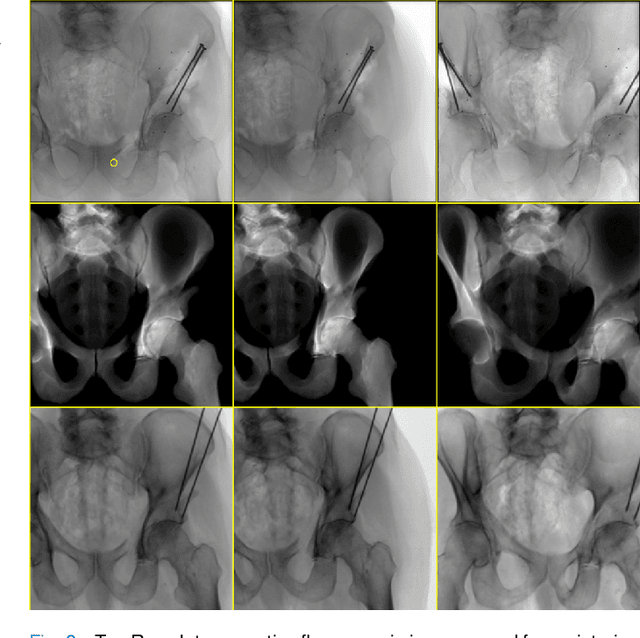

Abstract:Artificial intelligence (AI) now enables automated interpretation of medical images for clinical use. However, AI's potential use for interventional images (versus those involved in triage or diagnosis), such as for guidance during surgery, remains largely untapped. This is because surgical AI systems are currently trained using post hoc analysis of data collected during live surgeries, which has fundamental and practical limitations, including ethical considerations, expense, scalability, data integrity, and a lack of ground truth. Here, we demonstrate that creating realistic simulated images from human models is a viable alternative and complement to large-scale in situ data collection. We show that training AI image analysis models on realistically synthesized data, combined with contemporary domain generalization or adaptation techniques, results in models that on real data perform comparably to models trained on a precisely matched real data training set. Because synthetic generation of training data from human-based models scales easily, we find that our model transfer paradigm for X-ray image analysis, which we refer to as SyntheX, can even outperform real data-trained models due to the effectiveness of training on a larger dataset. We demonstrate the potential of SyntheX on three clinical tasks: Hip image analysis, surgical robotic tool detection, and COVID-19 lung lesion segmentation. SyntheX provides an opportunity to drastically accelerate the conception, design, and evaluation of intelligent systems for X-ray-based medicine. In addition, simulated image environments provide the opportunity to test novel instrumentation, design complementary surgical approaches, and envision novel techniques that improve outcomes, save time, or mitigate human error, freed from the ethical and practical considerations of live human data collection.